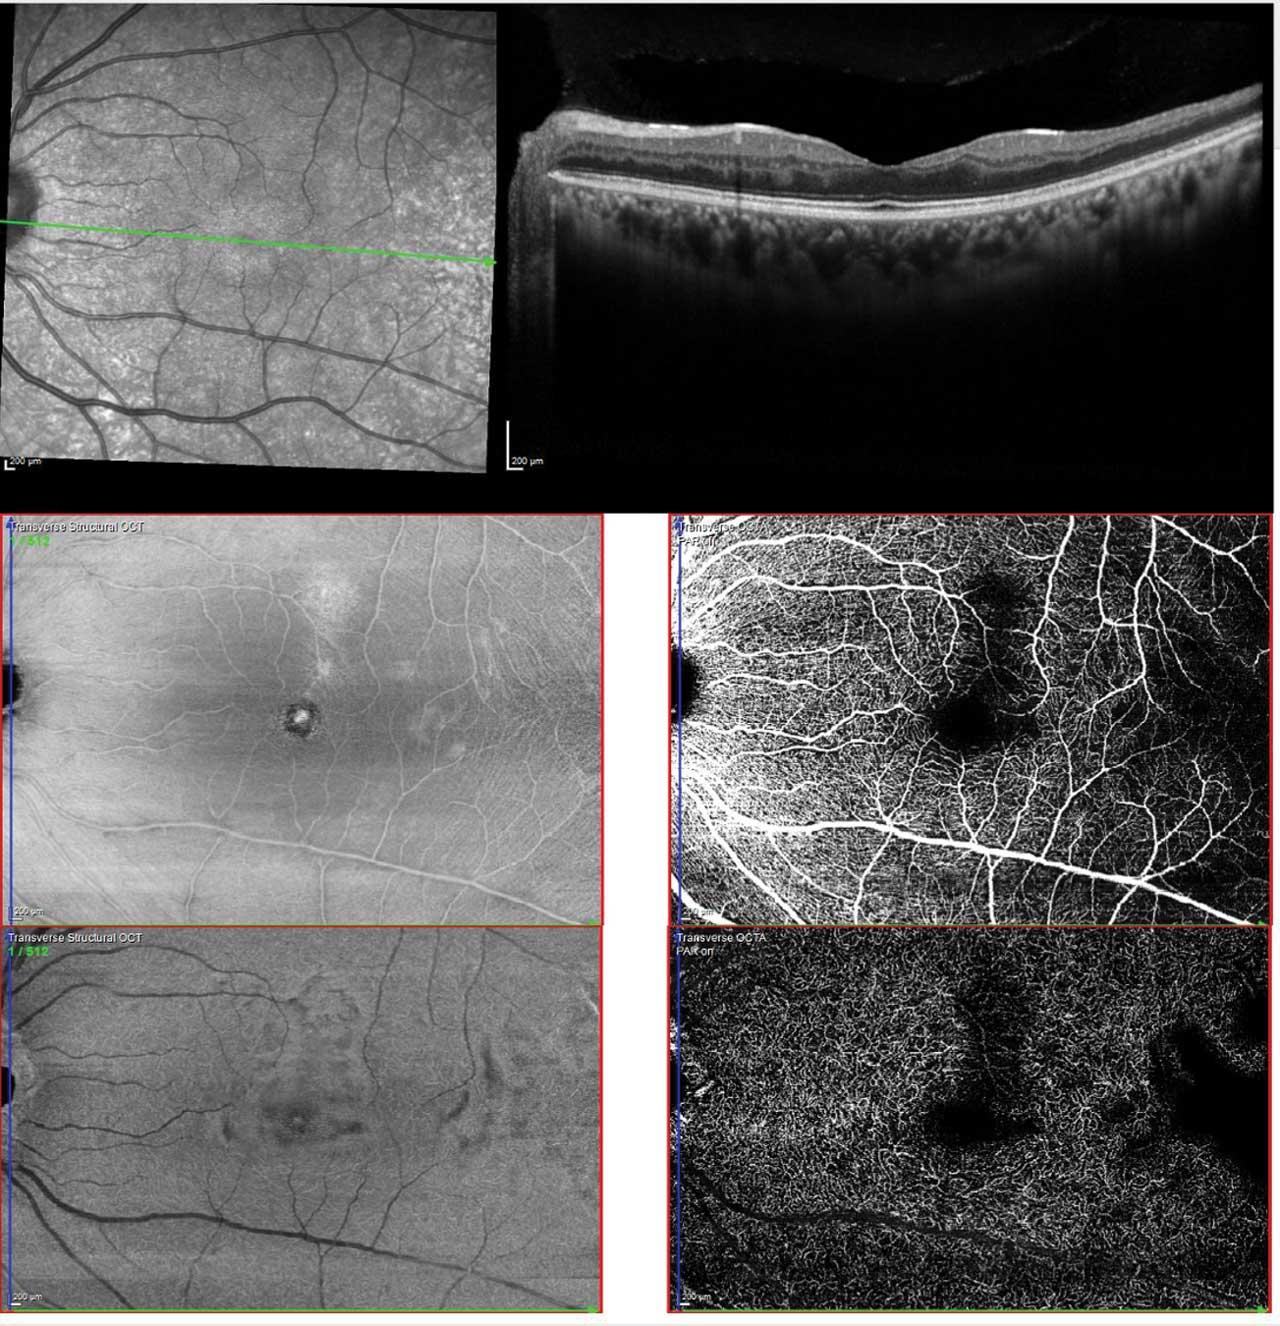

Screening remains exam first, but multimodal imaging now improves detection and monitoring (Figure 1).10 SD-OCT helps identify characteristic macular thinning or ischemic changes that may be clinically subtle.11 Ultrawidefield (UWF) color imaging expands peripheral assessment, and OCTA—ideally widefield when available—noninvasively quantifies macular/peripheral perfusion and correlates with disease stage, supporting earlier detection and objective follow-up (Figure 2).12 Fluorescein angiography is reserved for cases where treatment planning (eg, laser) requires defining peripheral nonperfusion or neovascularization.

Figure 2. Multimodal imaging of sickle cell maculopathy showing temporal parafoveal thinning on OCT (upper), reduced capillary density in the superficial plexus (middle), and marked capillary dropout in the deep plexus (lower). Photo by Katie Lachut-Yevich/VCU Health System.